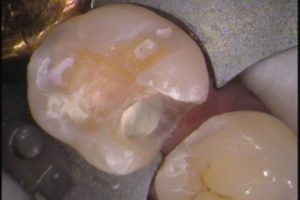

内部に白くなっている場所があります。

赤丸の所ですが、これは、つめ物です。

虫歯が大きかったので詰め物をして、神経を保護してあります。

黄色い、自身の象牙質が出てきました。

赤丸の場所が染まってきます。

赤丸の場所は神経との交通点です。

白く詰めたものがMTAセメントです。